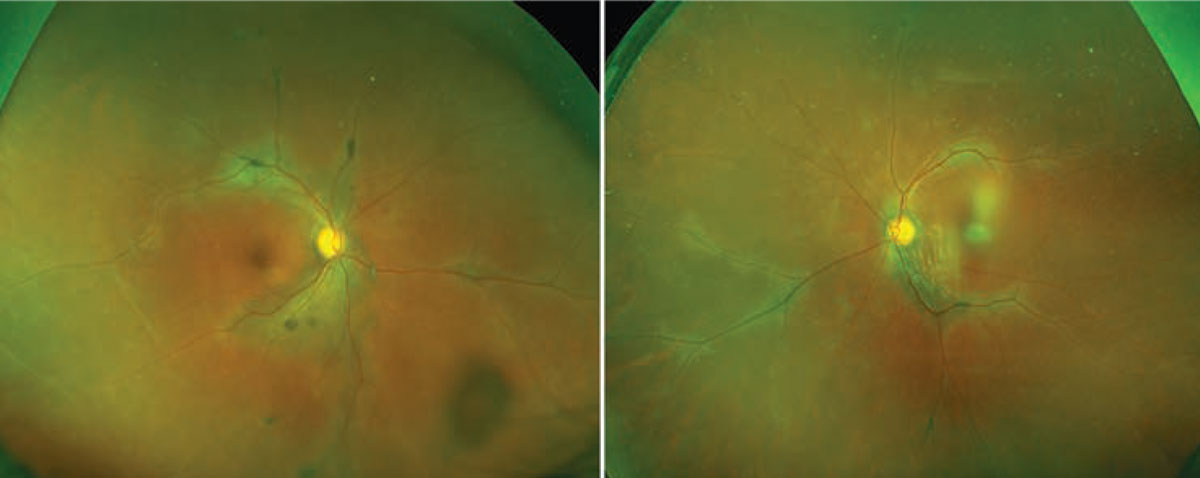

The fundus examination showed bilateral hypopigmentation emanating from the discs and extending out along the major superior and inferior arcades, with additional hypopigmentation noted along the nasal venules (Figure 1). Clumps of hyperpigmentation were also seen within the regions of hypopigmentation and were concentrated adjacent to the major retinal veins. A full scleral-depression exam showed no retinal tears or detachments or any vitreous snowballs or snow-banking in either eye.

Figure 1. Fundus examination shows multifocal areas of subretinal fluid bilaterally. |